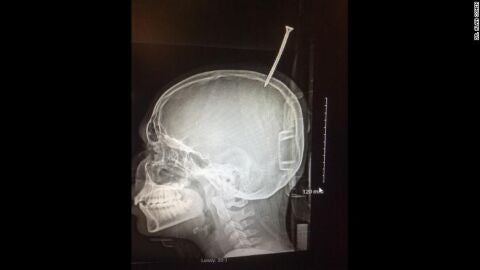

Un adolescente, "a un milímetro de morir desangrado" tras caerle una madera en la cabeza y que un tornillo se le clavase en el cráneo

El menor estaba construyendo una casa en un árbol en Maryland, EEUU, cuando un tornillo se le clavó en el cráneo. Un helicóptero tuvo que trasladarle de urgencia al hospital, donde los médicos aseguraron que si el tornillo se hubiera clavado un milímetro más, se habría desangrado.

Un niño de Maryland, EEUU, ha estado a punto de morir tras caerle un tablero de madera en la cabeza y un tornillo se le clavara en el cráneo. Darius Forema, de 13 años, tuvo que ser operado

El jefe de neurocirugía de la clínica John Hopkins y que atendió a Forema explica a la CNN que estuvo "a un milímetro de morir desangrándose".

Los médicos que participaron en la compleja operación tuvieron que intervenir al pequeño sin retirarle la tabla de madera hasta que fue completamente necesario. De hecho, antes de su traslado en helicóptero hasta el centro hospitalario, tuvieron que utilizar una motosierra para cortar parte de la madera, aunque no entera.

Afortunadamente, la operación salió bien y Darius ya se encuentra en casa con su familia.